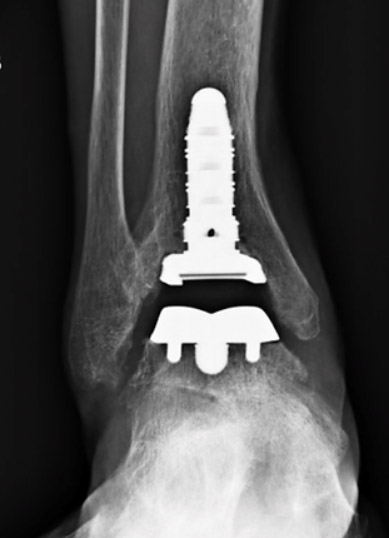

An example of an ankle replacement (total ankle arthroplasty) performed by Dr. Anthony Yi.

X-ray's of the same ankle before undergoing ankle replacement.